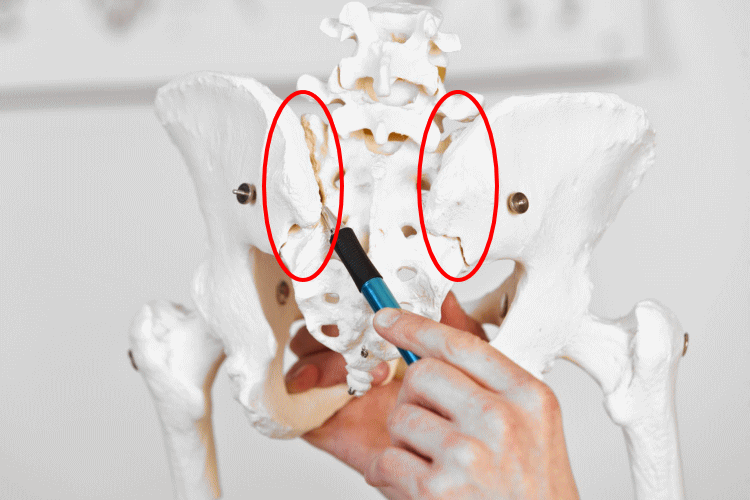

仙腸関節は、背骨(脊椎)のお尻側にある仙骨と、その両側の腸骨が接する関節であり、関節周囲の靭帯により、強固につながって骨盤を形成しています。

仙骨は仙腸関節が可動することで、呼吸や身体の動きに合わせて、僅かにですが、前屈、後屈、左右回旋…と動きます。ただ、画像検査ではわからない程度の動きです。2~3ミリ程度の可動域だといわれています。

この仙骨の動きがあるからこそ、骨盤は上半身のバランスをとりながら、また、骨盤へのクッション的存在として、下半身は上半身を支えることができるのです。

仙腸関節がほんのわずかズレたり、固着したりして関節の動きが障害されると、バランスやクッションの役割に支障が出るため、痛みやしびれが発症します。これを「仙腸関節(機能)障害」と言います。年齢や男女に関係なく、慢性腰痛の原因にもなります。